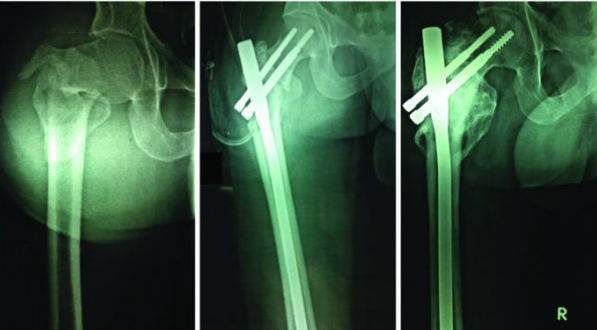

Comparison of Complications [Table/Fig-7]: Seven patients (30.4%) in the PFN group had an implant-related problem, whereas only one patient (4%) in the PFNA group had one [Table/Fig-8]. The difference in the rates of implant-related complications was found to be statistically significant (p=0.02). Both groups had one episode of deep infection, which was not deemed an implant-related consequence. One helical blade patient died from an unrelated medical cause.

Table/Figure 8: A 31.A3 fracture treated with a helical blade showing varus collapse of the fracture and medial migration of the blade at six weeks.

Complications in patients with Singh’s index ≤ 3: Three of the eight patients with considerable osteoporosis in the PFN group had implant failure, whereas none of the 13 patients with significant osteoporosis in the PFNA group had implant failure. This difference in complication rates was found to be significant (p=0.04) in the context of osteoporosis. Implant fracture, screw back out [Table/Fig-9], and Z effect were the problems encountered in these osteoporotic instances. The TAD and implant site were both optimal in the first two cases, and the Singh's grade was 3. The TAD for the Z-effect was 26.47 mm, and the Singh's grade was 2. Four patients with Singh's grade 3 had TAD > 25 mm in the PFNA group, but none of them suffered blade migration or failure.